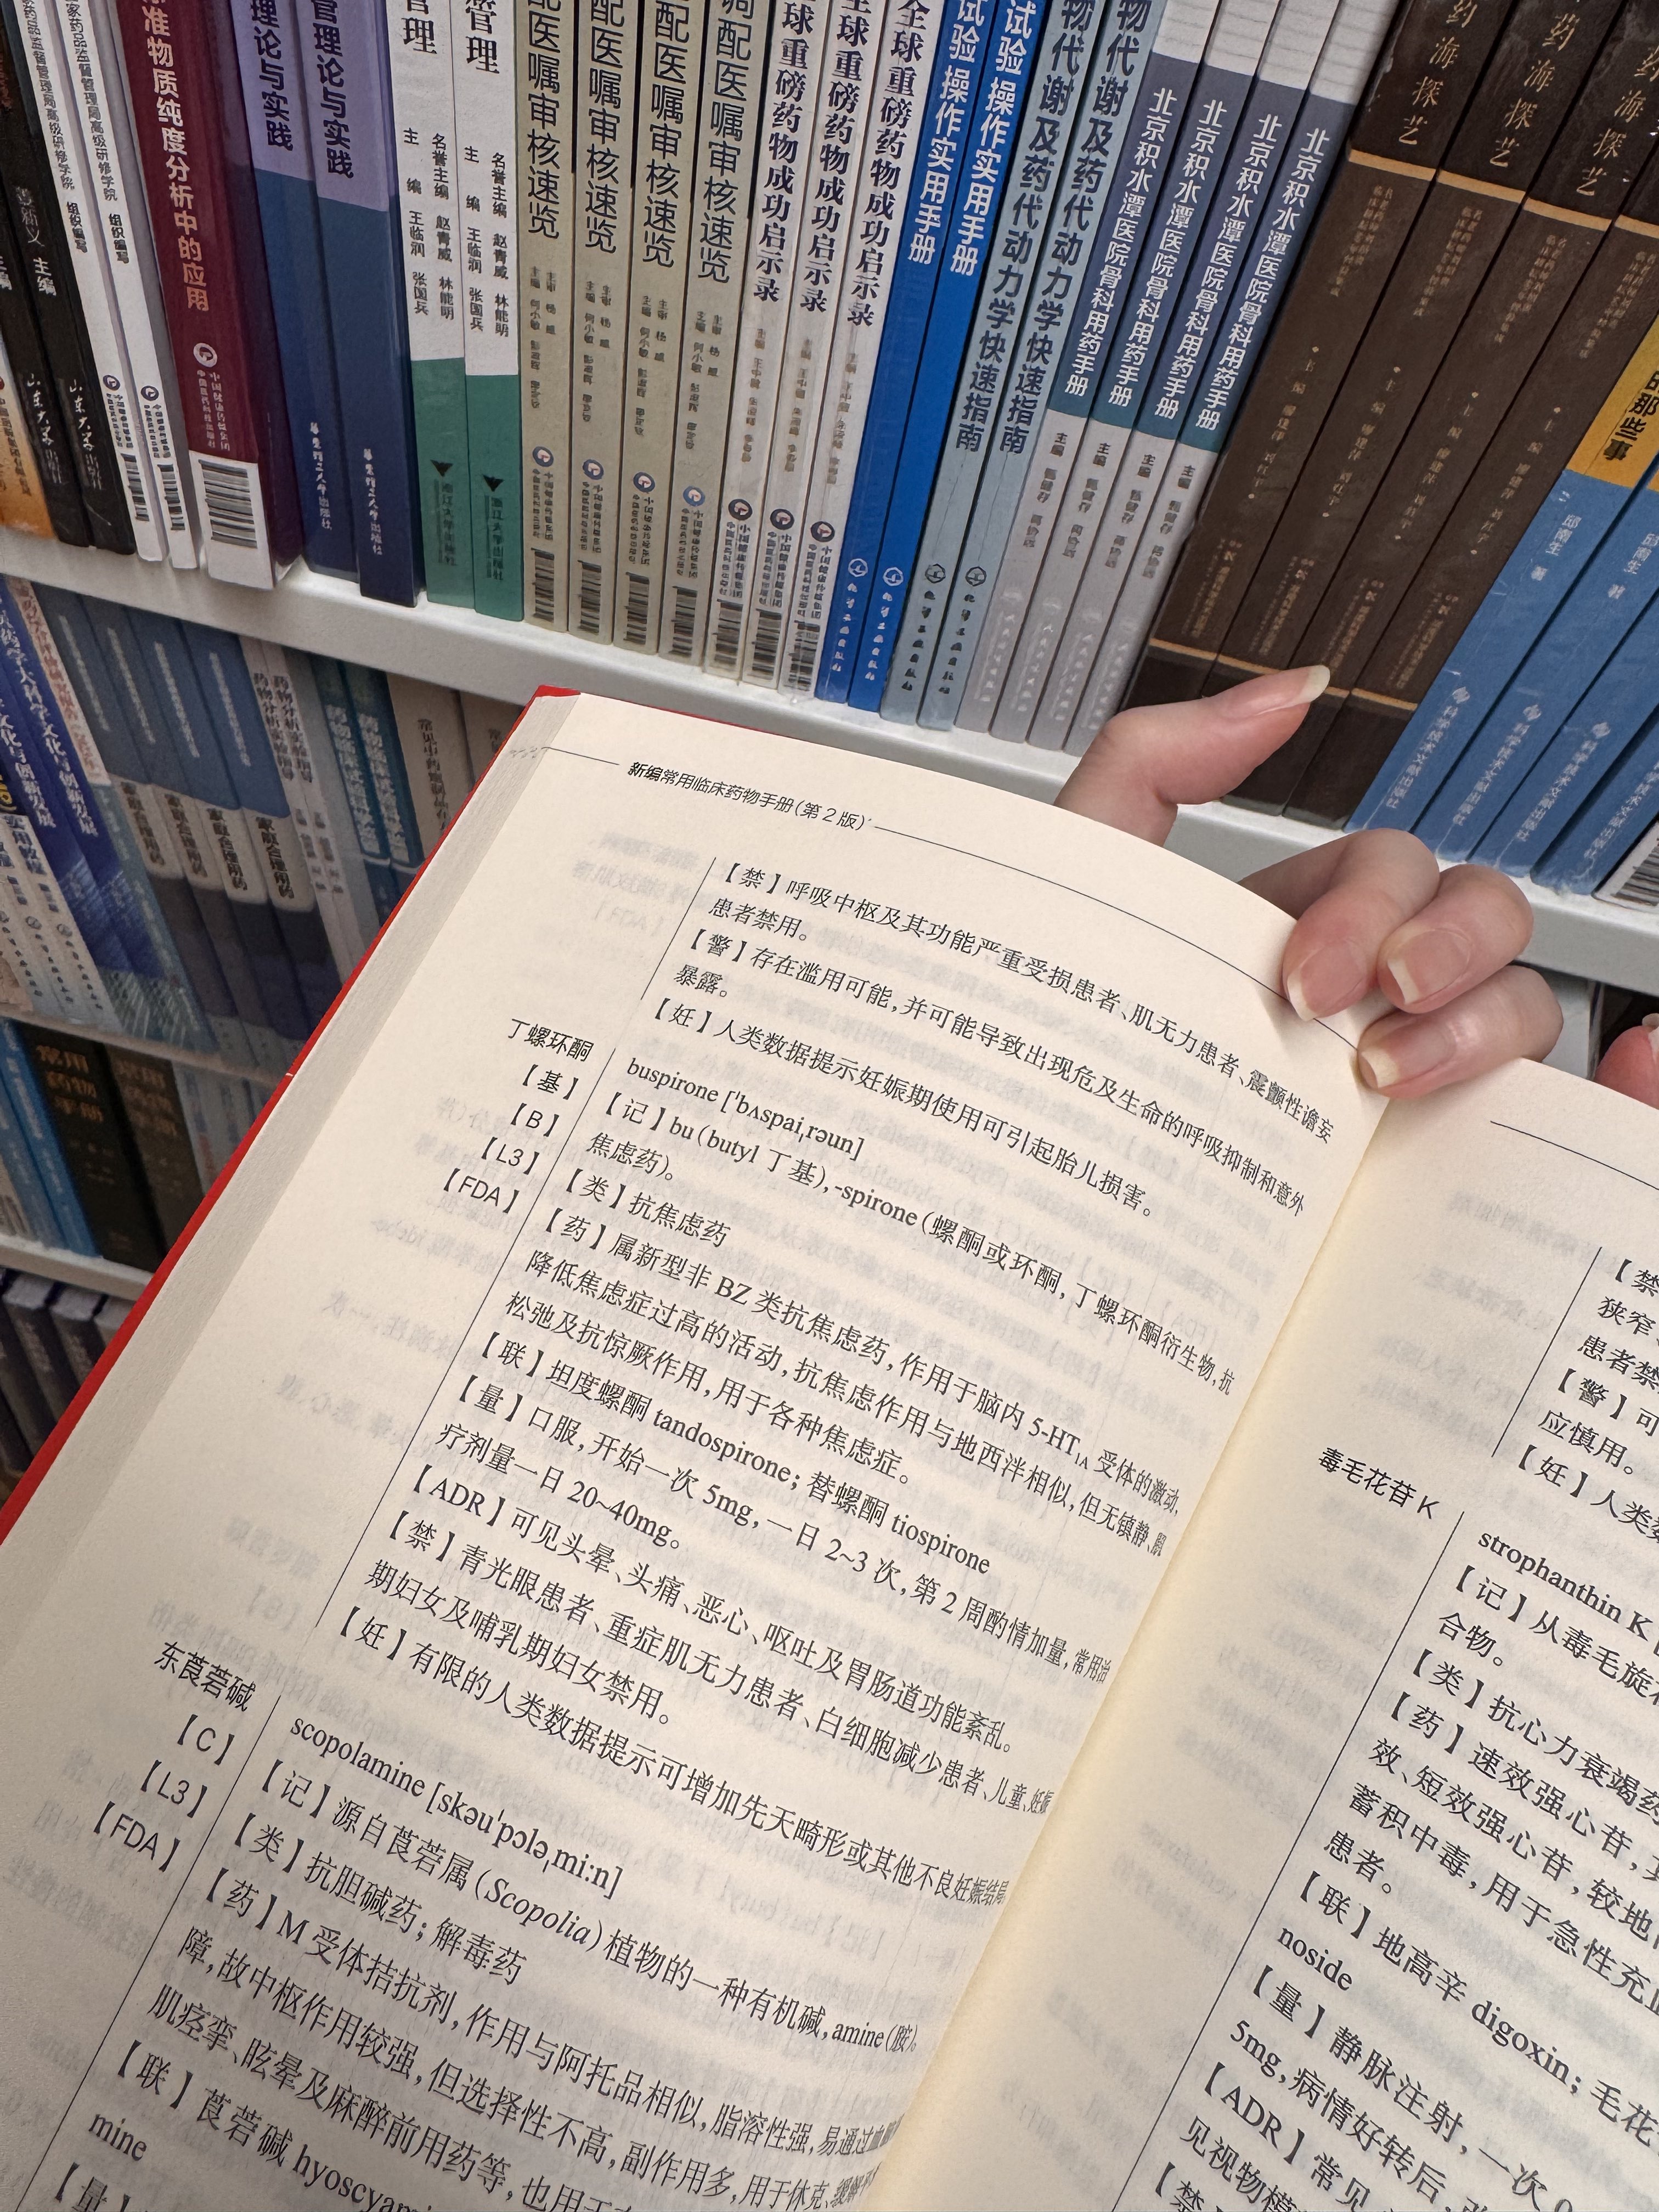

对于药物过量引起的中枢神经系统副作用,有一些不常见或常见的药物来控制症状。

罗通定:拮抗多巴胺

赛庚啶:血清素综合症

异丙嗪:在低剂量下没有抗精神病作用,和其他所有抗组胺药一样可以缓解过敏。止吐

喹硫平:不清楚是什么引起的症状就干脆谁都别玩了吧()似乎很万能的急救

评论区欢迎补充 https://t.co/7S4tGVDEM5